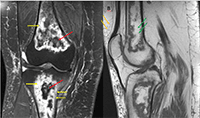

Ressonância magnética (RM) do joelho direito evidenciando lesões com aspecto geográfico acometendo grande parte das porções visualizadas da tíbia e do fêmur, caracterizando infartos ósseos. Em A, sequência DP com supressão de gordura (SG) no plano coronal mostra lesão com baixo sinal em sua porção central (seta vermelha), associada a edema adjacente (seta amarela). Em B, sequência T1 no plano sagital evidenciando lesão com margens serpiginosas e alto sinal no interior (setas verdes), provavelmente por conteúdo gorduroso (notar que o interior da lesão tem o mesmo sinal da gordura do tecido subcutâneo – seta laranja).